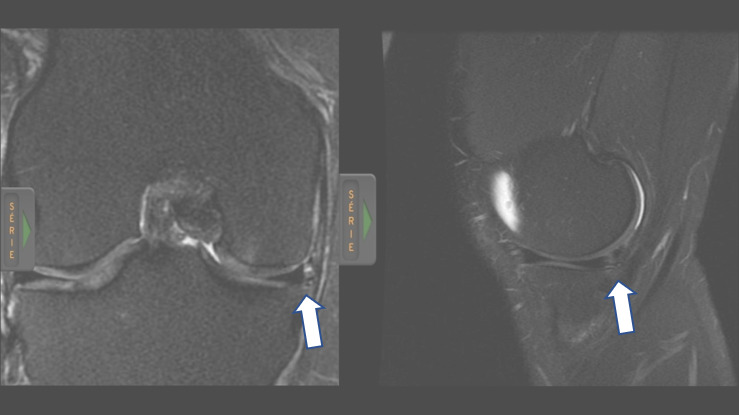

A 40-year-old man with a body mass index of 27.8 kg/m2 was referred for evaluation at the Laboratory of Biomechanics and Clinical Epidemiology of the University Hospital/UEL. During a soccer match, he suffered a contact injury of the right knee, clinically diagnosed as a meniscal tear. The MRI results indicated medial and lateral patellofemoral and tibiofemoral chondropathy, vertical/oblique rupture with a horizontal component characterized on the periphery of the posterior horn of the medial meniscus, and tendinopathy of the semimembranosus. From this, an exploratory meniscectomy was proposed by the surgeon responsible for the case; however, the patient opted for conservative treatment.